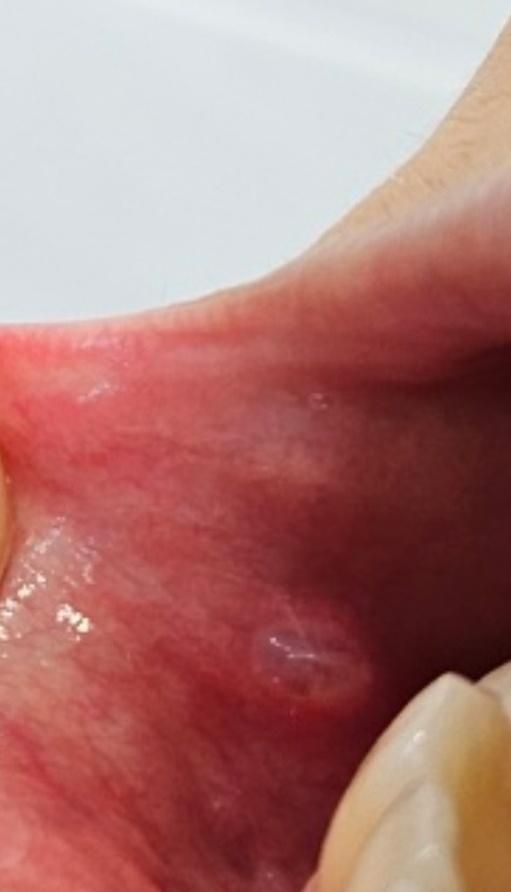

잇몸이 이상합니다 이빈인후과가봐야하나요(사진있고 혐오주의)

치과치료받던중(오른쪽) 기구들 왓다갓다하니

입안이 헐엇고

2주정도 아파습니다. 비타민. 연고. 입에뿌르는액체약 사용했고

오늘 오전까지만해도

티어나오지 않았습니다. 거의나았었고 불편감 없었거든요

근데 지금. 점심 먹고 이제 이닦으려고하는데

뭔가 있는 느낌들어서 확인했더니

저렇게 티어나왓습니다.(하얀염증 났던 곳)

건들면..살짝 아픕니다.

• 1번 째 사진

• 점액종으로 보입니다 점액종은 입막에 점막이 강한 자극을 받게 되면 내부의 조직액이 차서 생기게 됩니다 물집과도 같은 것인데 건들지 않으면 자연적으로 없어지게 됩니다 자세한 확인을 위해서 치과에서 진료를 받아 보는 것을 권해 드립니다

• 안녕하세요 치과의사 김철진입니다. 단순 자극에 의한 구내염인거 같습니다. 시간이 지나면 괜찮아 질테니 너무 걱정하지 않으셔도 될것같습니다.

• 치과 치료로 기구가 왔다갔다하면서 부터 현재와 같은 것이 관찰되었다면 단순 트라우마(trauma)로 인하여 나타난 구강 내 연조직 질환일 가능성이 큽니다. 이때는 특별히 치료를 할 필요는 없고 2주 정도 구강 내 자극을 줄여주는 것이 좋습니다. 다만 2주가 지났는대도 증상이 호전되지 않는다면 다시 치과를 방문하는 것이 좋습니다.

• 안쪽에서 피가 고인 혈종의 양상으로 판단되나 사진만으론 정확한 진단은 어렵습니다. 치과 치료 후 구강 내 생기는 혈종은 일시적인 현상이고 곧 괜찮아져서 특별히 신경쓰진 않아도 괜찮습니다. 보다 정확한 진단을 위해 구강내과가 있는 치과를 내원해보시면 됩니다.